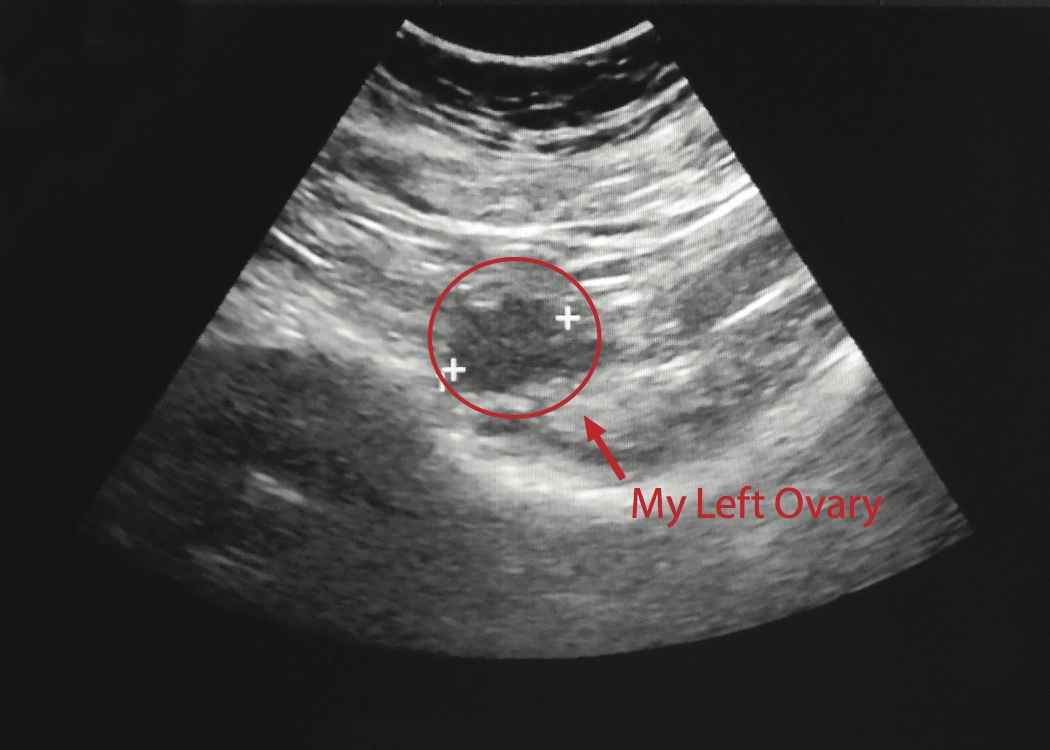

This is my left Ovary, which measured normal and looks great (size and cyst-wise)